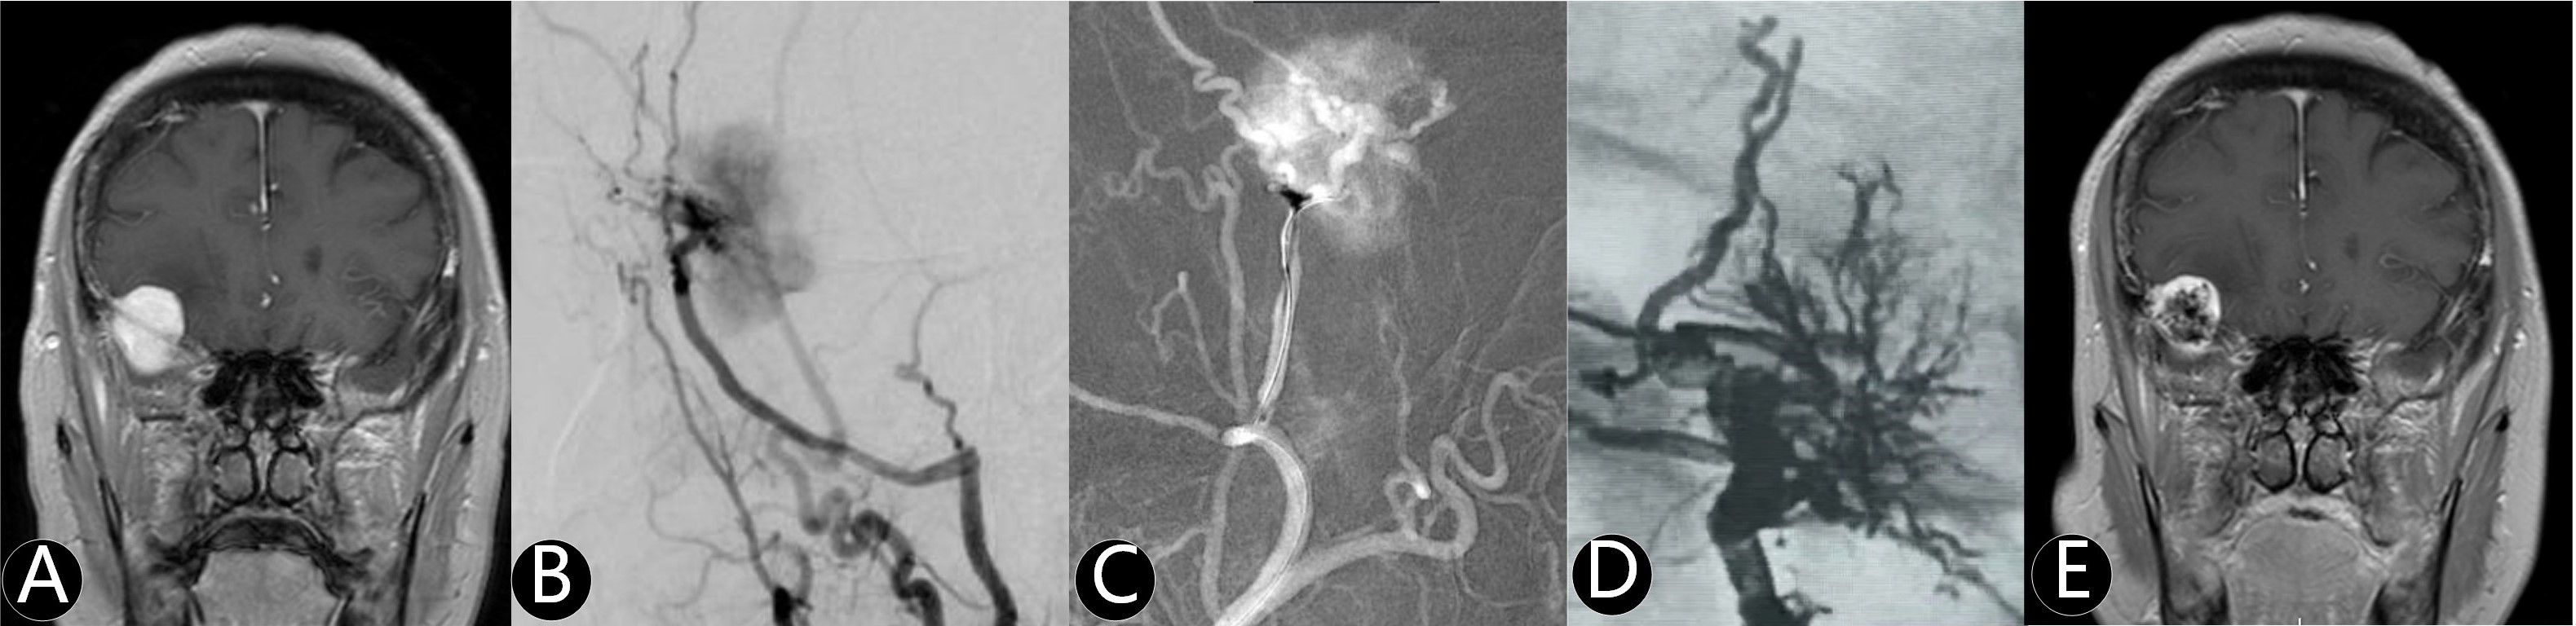

Background Preoperative embolization has been proposed to reduce intraoperative blood loss and facilitate meningioma resection, however its clinical utility remains debated. This multicenter study evaluated the safety, efficacy, and angiographic outcomes of preoperative embolization and standalone embolization in intracranial meningiomas. Methods In this retrospective cohort from January 2017 to January 2022, patients were stratified into three groups: standalone embolization (SE), combined preoperative embolization and craniotomy (hybrid surgery, HS), and craniotomy alone (control). Tumor characteristics, procedural metrics, and clinical outcomes were compared. Results: Compared to control group, the HS group exhibited significantly larger tumors (68.8±10.6 cm³ vs 35.7±11.3 cm³, P<0.001) but achieved reduced intraoperative blood loss (9.8±2.3 mL/cm³ vs 19.2±6.5 mL/cm³, P<0.001) and higher gross total resection rates (70.1% vs 46.2%; P=0.025). Compared to HS group, the SE cohort had smaller tumor volume (24.7 ± 5.2 cm³ vs 68.8 ± 10.6 cm³; P<0.001), better baseline neurological function score (median mRS 0 vs 1; P<0.001), and showed higher total devascularization rate (56.3% vs 25.4%; P=0.008) after embolization procedure. Tumors in SE group were supplied exclusively by the external carotid artery (ECA). At a median 24-month follow-up, recurrence rates and neurological change were no different across groups. Conclusion Hybrid surgery optimized surgical resection for large meningiomas by reducing blood loss and improving resection completeness, while standalone embolization demonstrated feasibility for select small tumors with ECA. Both two strategies showed acceptable safety and effectiveness.